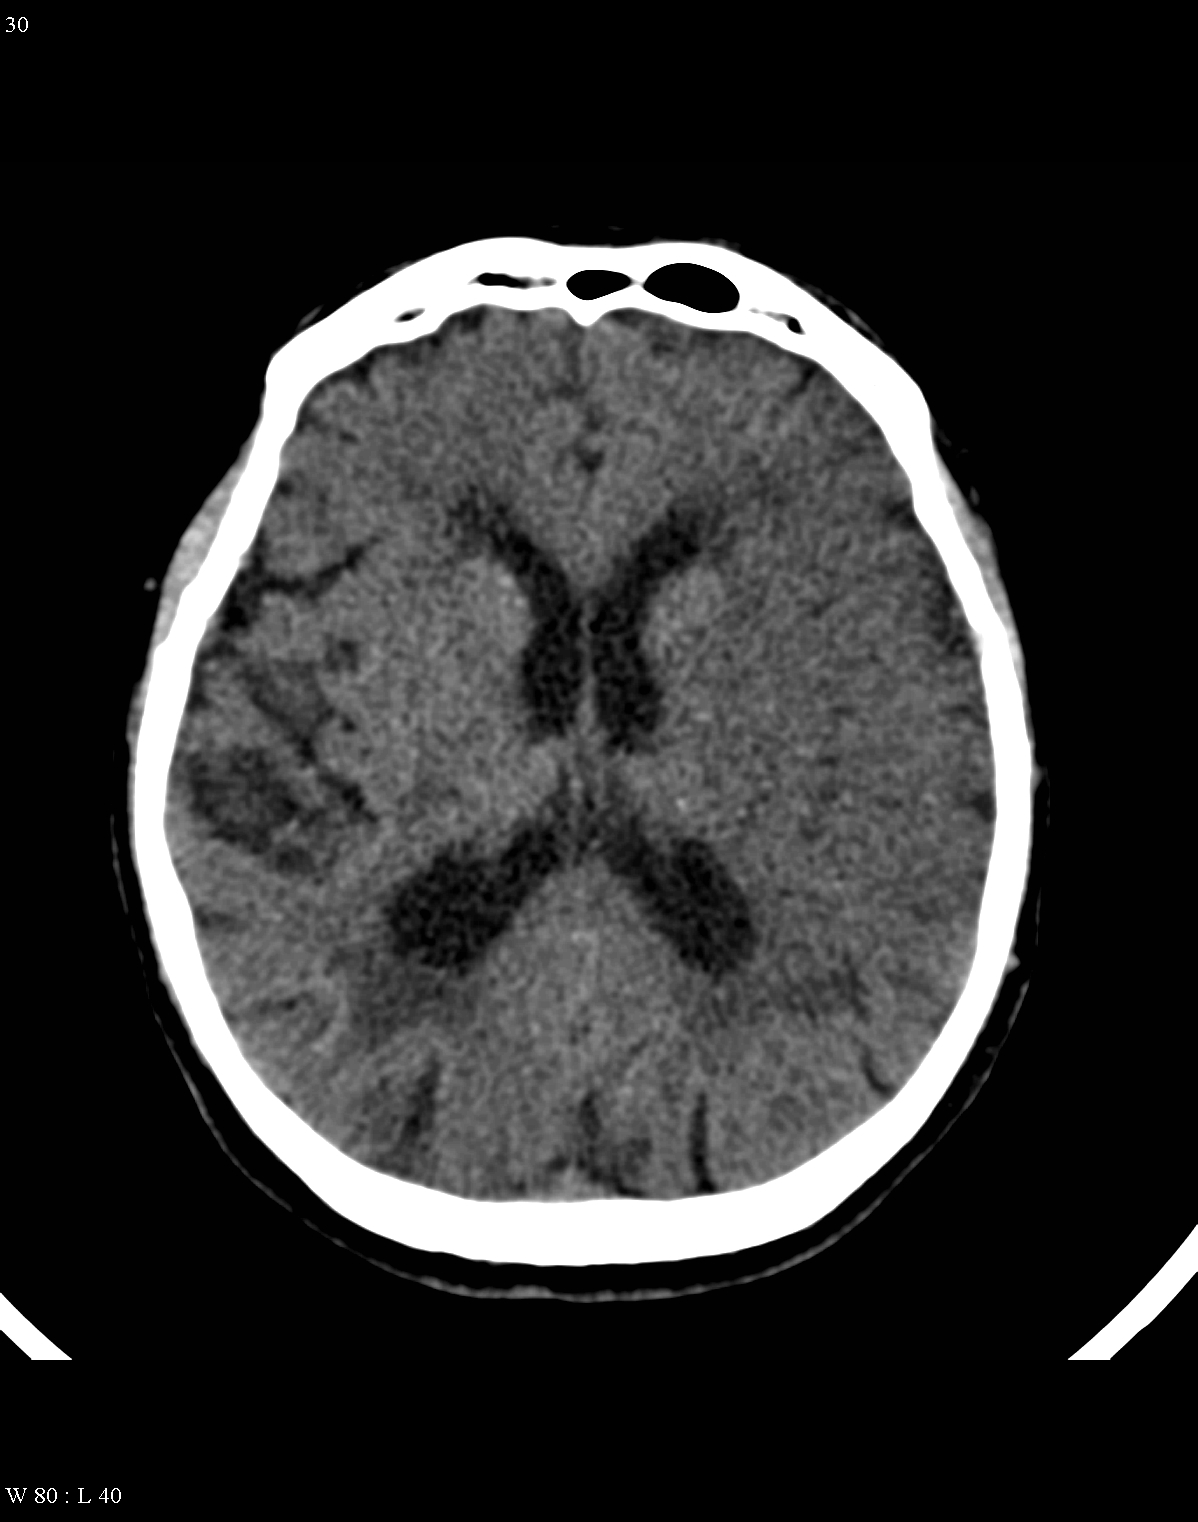

On CT images acute bleeding always presents as hyperdensity. (One has to keep it mind that hyperdensity of the blood is affected by the hematocrit levels, hence making the diagnosis more difficult.) Intraparenchymal blood is dominated by a destructive appearance (mass-effect) and it is surrounded by hypodensity as a sign of perifocal edema. It often breaks into the ventricles. In patients lying in a supine position they collect (sediment) at the occipital horn of the lateral ventricles, creating a hyperdense liquid-to-liquid levels. Later on, the density of blood decreases and shows a peripheral ring or rim-like contrast enhancement without mass-effect.

Although, subarachnoid hemorrhage (SAH) is most often caused by the rupture of a berry aneurysm, arteriovenous malformation (AVM) and trauma can also lead to it. SAH is typically located at the basal subarachnoid spaces, which then propagates along the lateral fissures or it fills up the interhemispheric fissure till the convexities. The main collection of the blood is usually indicative of the source of origin. In cases of parenchymal spread the mechanism, whether it broke in, or it broke out from the parenchyma could represent a differential diagnostic challenge. When accompanied by brain edema, the consequent herniation can result in parenchymal infarcts as well.

CT angiography examination is usually advisory in order to confirm the site of the bleeding. It is also effective when a hemorrhagic tumor is in the differentials, although complete differentiation might only be achieved by follow-up examinations. CTA is also essential in the diagnostics of multiple aneurysms (which are prevalent in 20-30% of the cases based on autopsy reports.) In case of a subarachnoid hemorrhage the consequently developing hydrocephalus and its degree might only be detected on follow-up CT examinations. It is very important to note that an initial brain aneurysm rupture might be followed by a second one within the first 7 – 10 days and the resulting vasospasm carries a much higher risk of mortality than the one at the time of the first SAH. This is why the scrutonius review of the acute diagnostic imaging is essential and it plays a fundamental role in patient treatment. Open brain surgery of the aneurysm (clipping) has been replaced by catheter angiography (DSA) nowadays. The aneurysm is either filled up with thrombogenic coils through its neck or recently bypassing stents are inserted to exclude the aneurysm from the cerebral circulation.